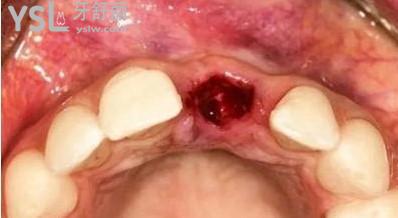

▲ 刚拔掉牙齿的样子:

▲